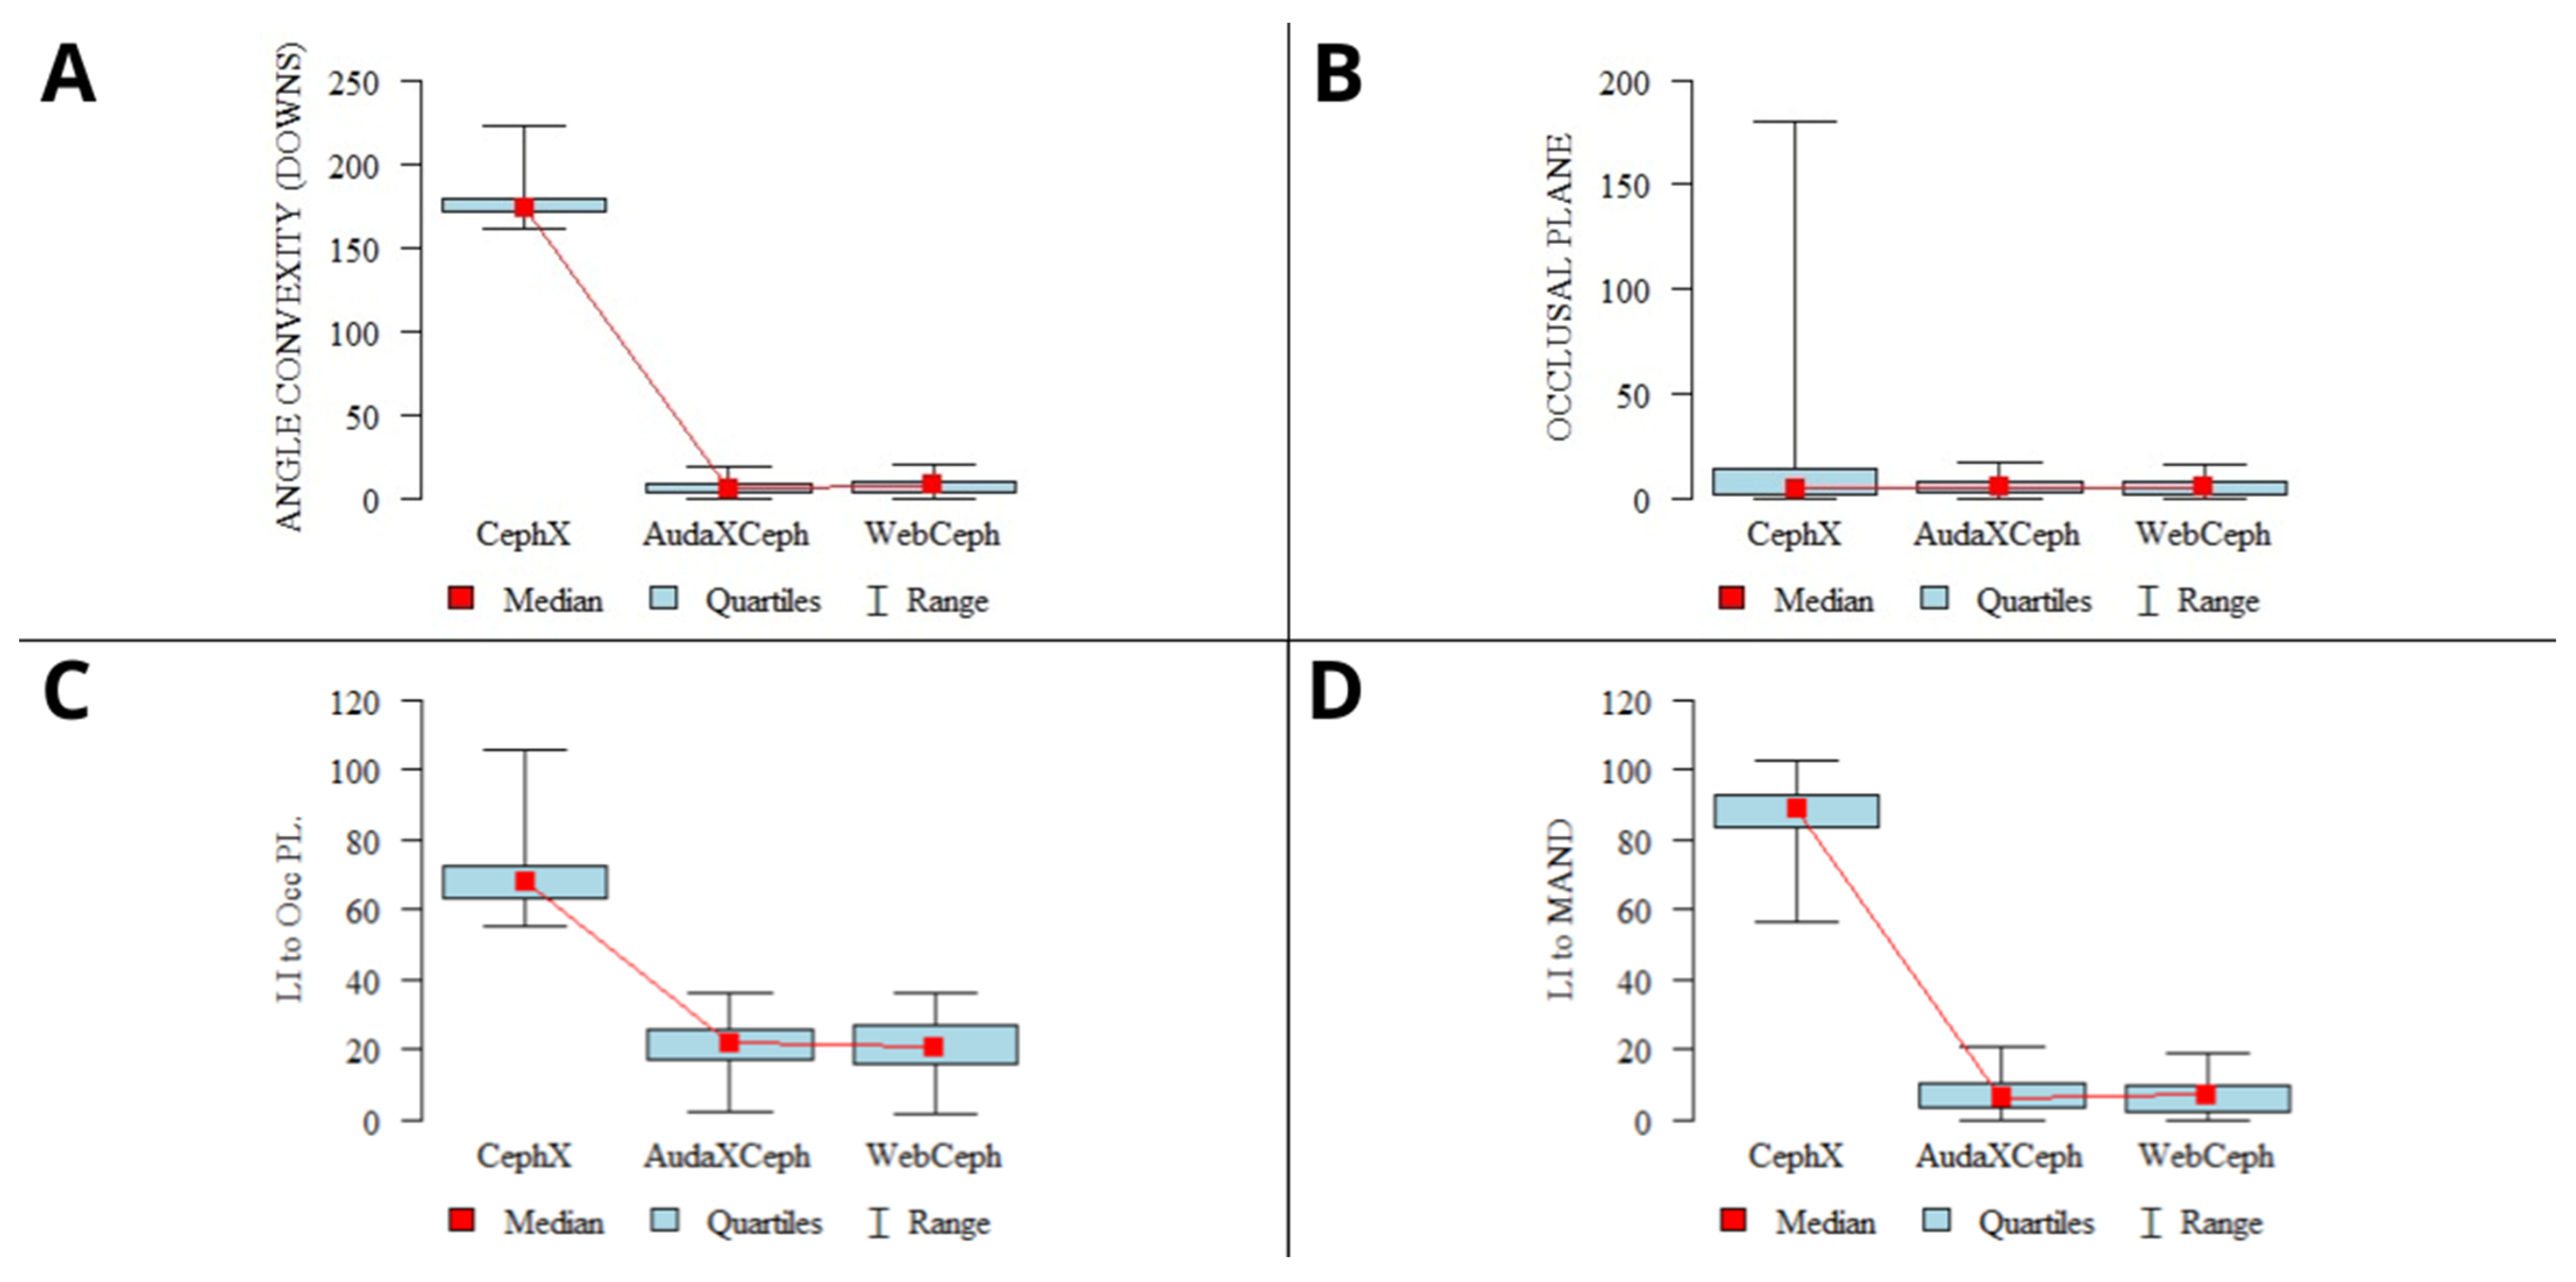

| ANGLE CONVEXITY (DOWNS) | CephX-A | 176.32 | 10.41 | 174.00 | 161.78 | 222.66 | 171.13 | 179.30 | p < 0.001 * A > C > B |

| AudaXCeph-B | 7.18 | 4.53 | 6.28 | 0.66 | 19.68 | 3.77 | 9.69 | ||

| WebCeph-C | 7.99 | 4.51 | 7.88 | 0.50 | 20.43 | 4.10 | 10.96 | ||

| OCCLUSAL PLANE | CephX-A | 42.80 | 72.23 | 5.53 | 0.13 | 179.93 | 1.65 | 13.98 | p = 0.01 * A > C |

| AudaXCeph-B | 6.11 | 4.01 | 5.38 | 0.32 | 17.61 | 3.21 | 8.38 | ||

| WebCeph-C | 5.86 | 4.05 | 5.27 | 0.09 | 16.65 | 2.50 | 8.48 | ||

| LI to Occ PL. | CephX-A | 69.23 | 8.33 | 67.93 | 55.17 | 105.49 | 63.26 | 72.47 | p < 0.001 * A > B.C |

| AudaXCeph-B | 20.31 | 7.30 | 21.70 | 2.32 | 36.02 | 17.22 | 25.68 | ||

| WebCeph-C | 20.62 | 7.52 | 20.76 | 1.88 | 36.08 | 16.00 | 27.19 | ||

| LI to MAND | CephX-A | 87.13 | 7.93 | 88.60 | 56.63 | 102.33 | 83.69 | 92.10 | p < 0.001 * A > C.B |

| AudaXCeph-B | 6.98 | 4.72 | 6.35 | 0.09 | 21.00 | 3.53 | 9.73 | ||

| WebCeph-C | 6.87 | 4.48 | 7.39 | 0.13 | 18.85 | 2.79 | 9.56 | ||